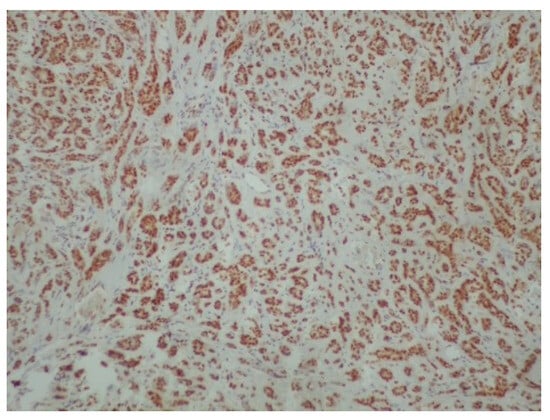

Figure 5.

Diffuse and intense positivity of neoplastic cells for S100 protein (immunoperoxidase ×100).